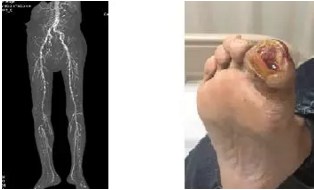

透析患者下肢血管钙化 糖尿病足

针对透析室近期几位患者接连出现下肢动脉狭窄或糖尿病足感染,有的甚至需要截趾手术,12月21日晚5点肾内科联合血管外科、放射科、皮科、超声科共同召开了尿毒症患者下肢血管病变及足部感染讨论会。会议由李月红主任主持,肾内科李敏侠医师结合具体病例,针对透析患者血管病变和足部感染高发的原因向与会专家进行了详细介绍;放射科郑卓肇部长详细介绍了血管病变检查的影像学进展,阐述了核磁和血管造影的优缺点,及评判感染是否侵犯骨髓的影像学特点;皮肤科赵邑主任介绍了局部抗感染,促进皮肤愈合的组织生物学、生长因子和药物等新进展。血管外科赵俊来和曹战江医师讲述了血管外科最新的血管病变介入手术方法及糖尿病足的处理原则。与会医师均觉得受益匪浅,表示成立多学科诊疗中心共同管理患者,相信在北京清华长庚医院多学科专家的共同管理下,透析患者一定会拥有更健康美好的生活。